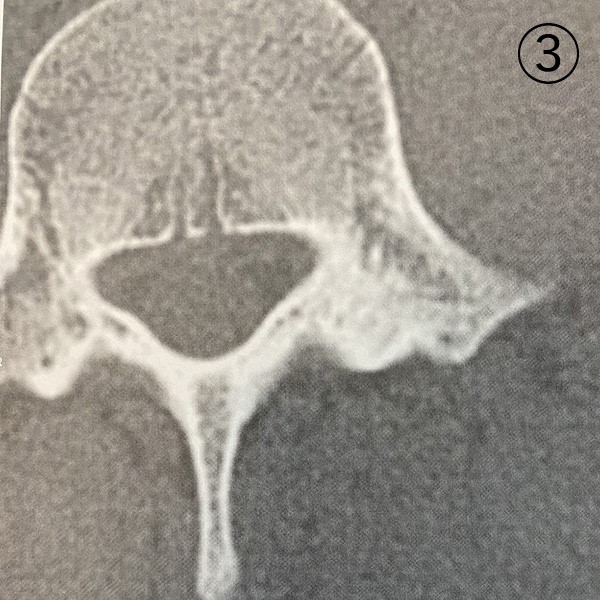

レントゲン写真

2ヶ月後のCT画像